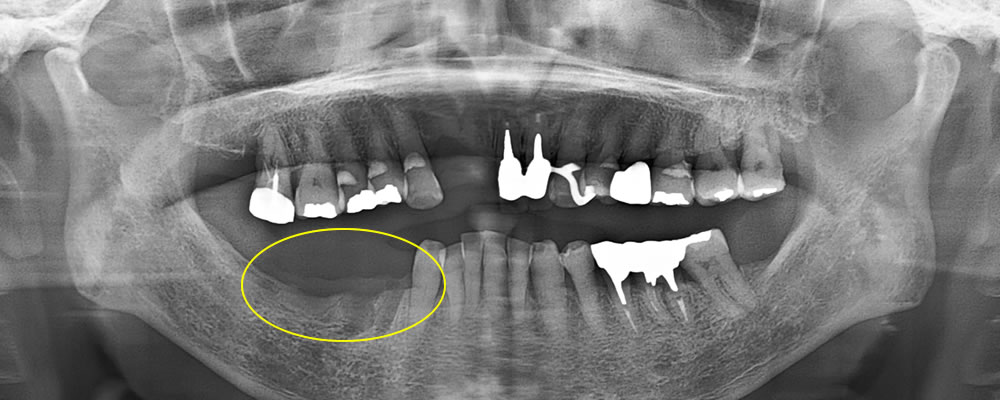

こちらの患者さまは、右下奥から2番目の歯が噛んだ時に痛いとの主訴で来院されました。

レントゲン写真にて、右下6番歯の歯根周囲に透過像を認めました。口腔内を確認したところ、メタルインレー下に二次う蝕を認めました。また、歯周ポケットは10mmと深く、歯根破折が疑われたため、補綴物を除去して精査することとなりました。

メタルインレーの除去

当該歯のメタルインレーを除去したところ、歯の内部に2次カリエス(虫歯の再発)を認めました。

う蝕検知液(虫歯部分に着色する薬液)を使用しながら、慎重に虫歯除去を行ったところ、遠心に歯根破折を確認しました。歯周ポケットが深かった部位と破折線が一致しており、このままつめ物を装着しても予後不良となる可能性があることを患者さまに説明したところ、抜歯とインプラントによる治療を希望されました。

また、他の銀歯の下にも複数の二次カリエスが認められたため、患者さまは口腔内全体の銀歯を除去し、再治療を行うことを希望されました。